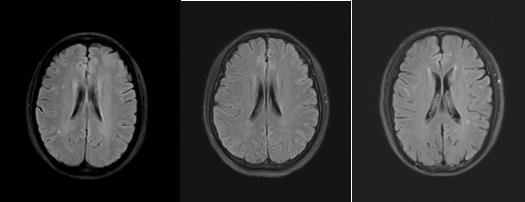

(FLAIR序列及T2WI序列显示缺血性脱髓鞘病变)

(常见无症状炎性脱髓鞘病变)